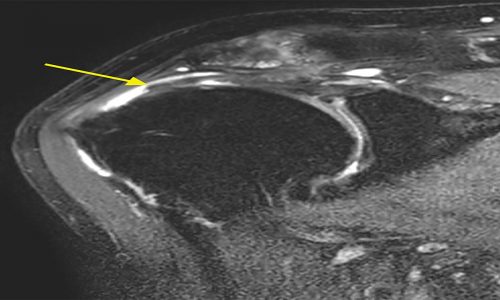

Η διάγνωση γίνεται με την κλινική εξέταση που βασίζεται σε ειδικές δοκιμασίες και επιβεβαιώνεται με απεικονιστικό έλεγχο που περιλαμβάνει ακτινογραφίες, υπερηχογράφημα και μαγνητική τομογραφία.